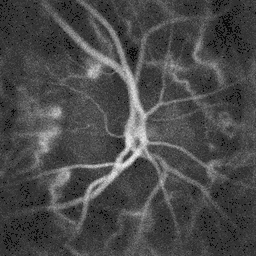

![]() Pulsatile blood flow in the central retinal artery revealed by laser Doppler holography | |

The central retinal artery supplies blood to all the nerve fibers that form the optic nerve, which carries the visual information to the lateral geniculate nucleus of the thalamus, including those that reach over the fovea. Its blood flow can be revealed by fluorescein angiography or laser Doppler imaging.[4]